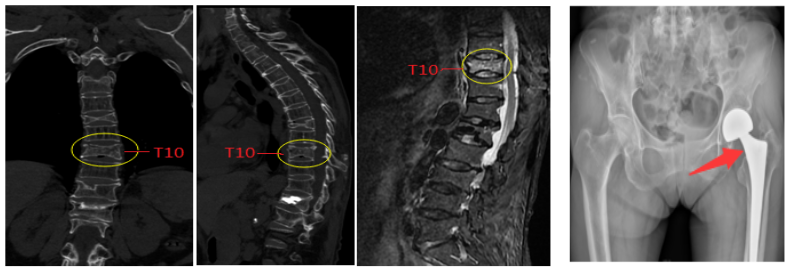

2020年03月11日,正值全国人民抗击新冠病毒肺炎迎来新希望之际,全国各大城市复工复产有序分批分次进行中。阿坝州人民医院骨科迎来一位特殊患者,该患者为72岁女性,4年前于外院行“腰1椎体骨折经皮椎体成形术”,2年前行“左侧全髋关节置换术”, 既往还有“胸8椎体陈旧性骨折”。此次因“摔倒致胸背部疼痛、活动受限26天”入院,诊断为“胸10椎体骨质疏松性骨折”。

一切准备就绪,患者于2020年3月14日在局麻下进行了“胸10椎体骨折经皮椎体成形术”,用时仅仅34分钟,手术成功。